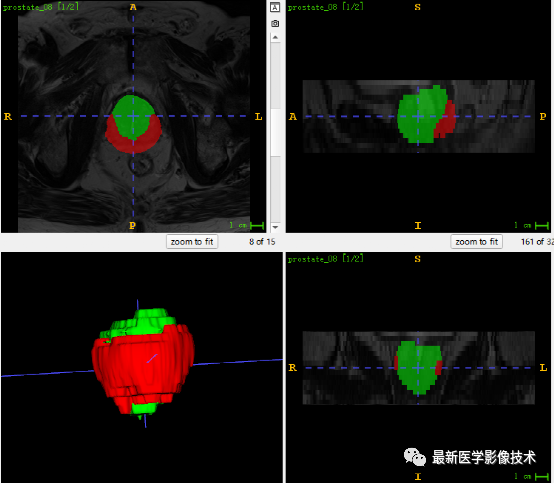

5、验证集分割结果

左边是金标准结果,右边是网络预测结果。